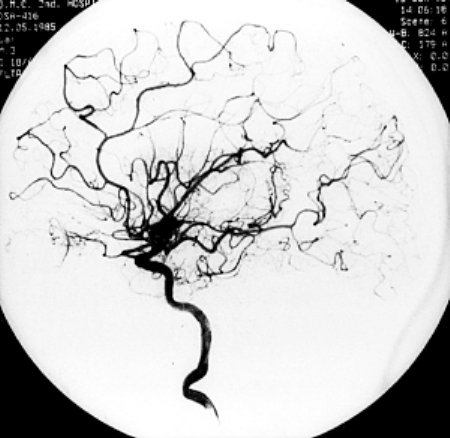

•血管造影:1至3小时

血管造影:注入造影剂有时会有温暖或灼热的感觉。造影剂可能引起恶心,呕吐,潮红,瘙痒或口苦等症状。在极少数情况下,人们会对造影剂产生严重的过敏反应,影响患者的呼吸和血压。造影剂也会引起肾脏问题,这种情况很少见,但在肾功能不全的患者中较常见。

该检查存在一种小风险的可能,就是在导管末端有可能会形成血凝块的,阻塞血管。导管损伤血管的风险也很小,但这可能导致内出血。如果按压时间过短,可能会导致创口出现血肿(皮肤下聚集大量血液)。除此之外,创口部位可能存在感染的几率。

你的身体可能会因为躺在操作台上几个小时而感到疼痛。